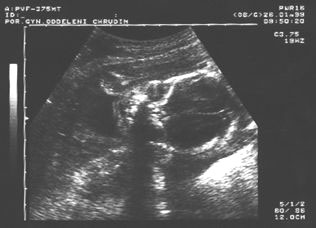

14. týden: páteř plodu

14.týden